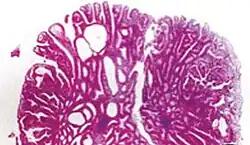

| Tubular adenoma | 2% at 1.5 cm[12] | Low to high grade dysplasia[13] | Over 75% of volume has tubular appearance.[14] |

|

Neoplastic polyps of the bowel are often benign hence called adenomas. An adenoma is a tumor of glandular tissue, that has not (yet) gained the properties of cancer.

The common adenomas of the colon (colorectal adenoma) are the tubular, tubulovillous, villous, and sessile serrated (SSA).[18] A large majority (65–80%) are of the benign tubular type with 10–25% being tubulovillous, and villous being the most rare at 5–10%.[9]